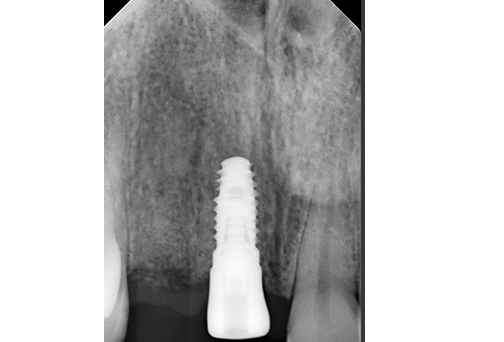

The fixed cantilever bridge was inserted, and seating was verified with a periapical X-ray. Torqued to 20 Ncm. Contacts were checked, and occlusion was adjusted. Final photographs and a scan were taken for the records.

Images were taken at the insertion appointment. Soft tissue healing remains ongoing.